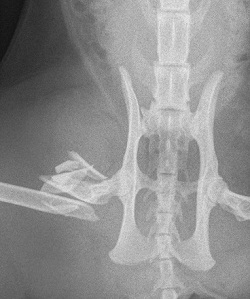

Feline femoral fracture repaired using a tied in external fixator with cluster pin technique in the proximal femur